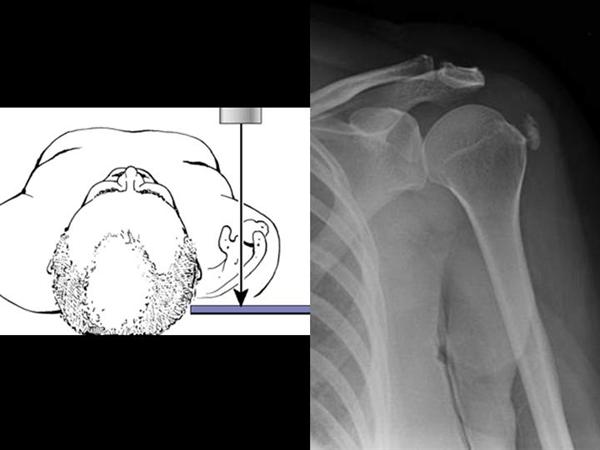

3. axillary lateral view

팔이 안벌어지는 경우에는 velpeau view 를 촬영해 볼 수 있습니다.

상완골의 탈구/아탈구 를 확인해 볼 수 있습니다.